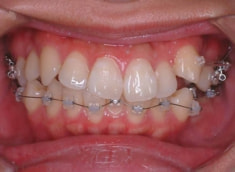

治療後(2年6ヶ月後)

治療後のセファロ分析

前歯の位置、傾斜、Eラインなど、改善が認められます。

治療後のセファロ分析正貌

非対称が解消されております。